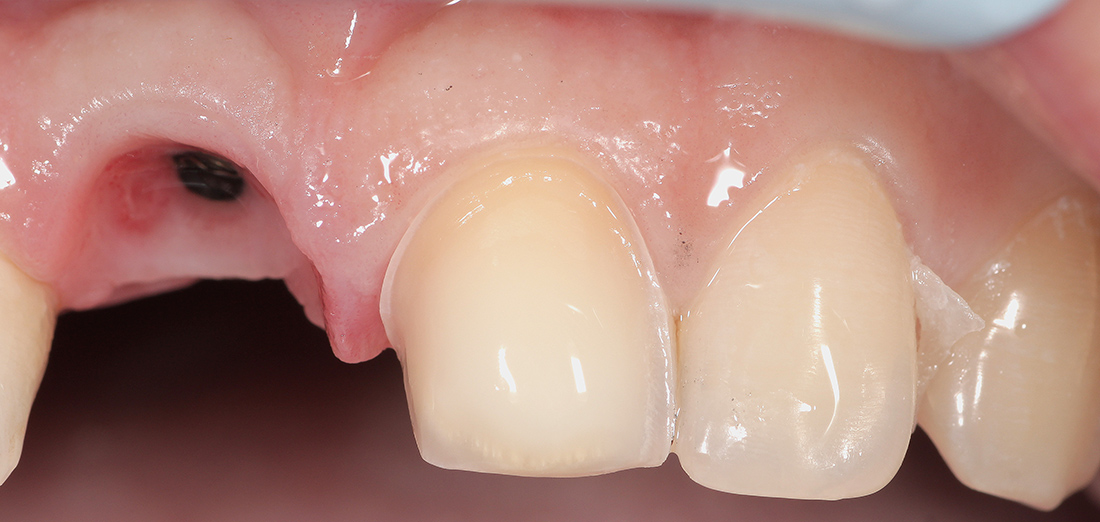

Под местной анестезией был удален зуб, установлен имплант, проведена пластика мягких тканей и фиксирована временная коронка. Через три месяца проведена оценка импланта, и мы перешли к замене временной коронки на постоянную. Опорой для коронки на импланте послужил индивидуальный циркониевый абатмен.

Для закрытия диастемы- промежутка между центральными зубами, было решено дополнительно изготовить винир на соседний зуб. Коронка и винир были изготовлены из цельнокерамического материала E.Max Press, позволяющего создать наиболее естественные и эстетические реставрации. Фиксация ортопедических конструкций была проведена за один этап.